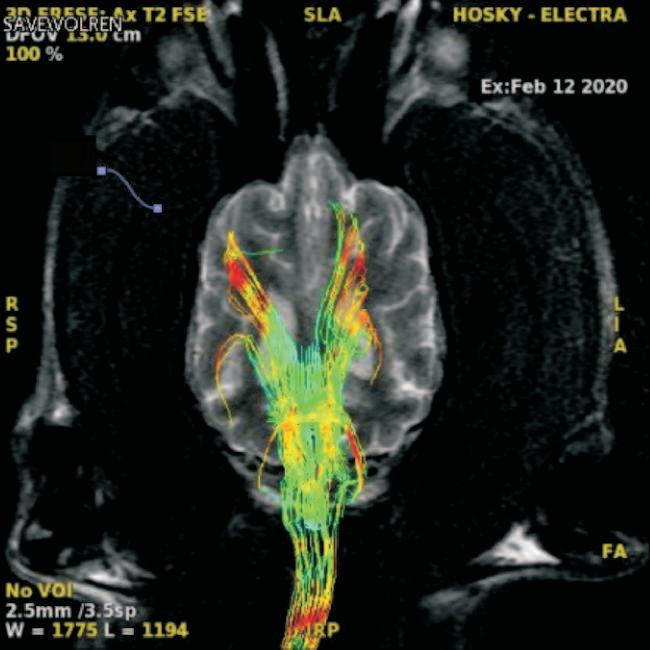

Uso del tensor de difusión como una herramienta de diagnóstico en las enfermedades del sistema nervioso central en perros. Reporte de un caso en un husky siberiano con alteraciones del comportamiento.

José Alberto Toscano-Zapién, Patricia Rizo-Espinoza, Ismael Hernández-Avalos, Liliana Blancas-Espinoza, Erick Humberto Pasaye-Alcaraz, Edna Elisa García-Vences, Raúl Silva-García

Use of the diffusion tensor as a diagnostic tool in diseases of the central nervous system in dogs. Report of a case in a Siberian husky with behavioral alterations. .